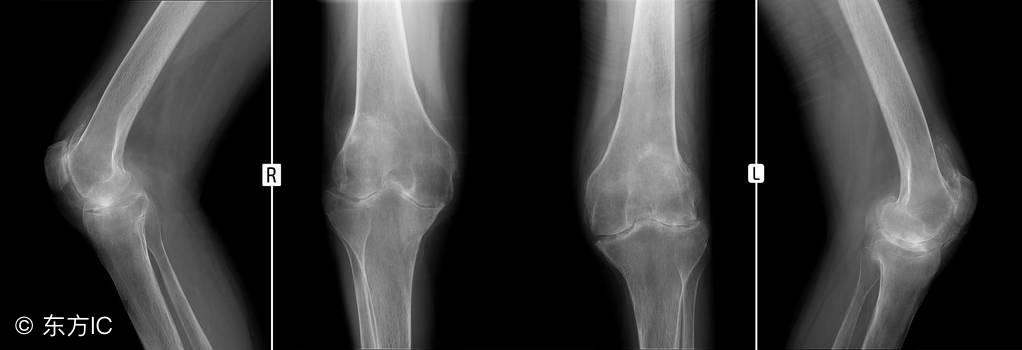

诊断骨关节炎主要靠拍片子, 拿膝关节为例,主要有四个特点: 骨质增生,关节面硬化、关节间隙变窄以及临关节囊性变。